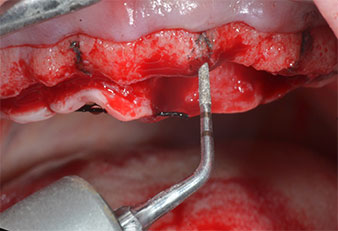

Un insert piézoélectrique diamanté de forme effilée (Piezomed I1) a été utilisé pour marquer les positions implantaires et effectuer la préparation pilote (Fig. 3). On a pris soin de travailler selon un mouvement ascendant et descendant, à puissance réduite, irrigation complète et basse pression (moins de 300g). Ensuite, un insert pilote (Piezomed I2A/I2P) a été utilisé pour l’agrandissement initial de 2mm du diamètre des sites implantaires (Fig. 4), suivi d’un insert de 3mm (Fig. 5).

Insert marqueur à ultrasons Piezomed

Fig. 3 : L’insert marqueur à ultrasons Piezomed I1 sert à effectuer la préparation selon un mouvement ascendant et descendant, parallèlement à l’axe le plus long de la partie active.